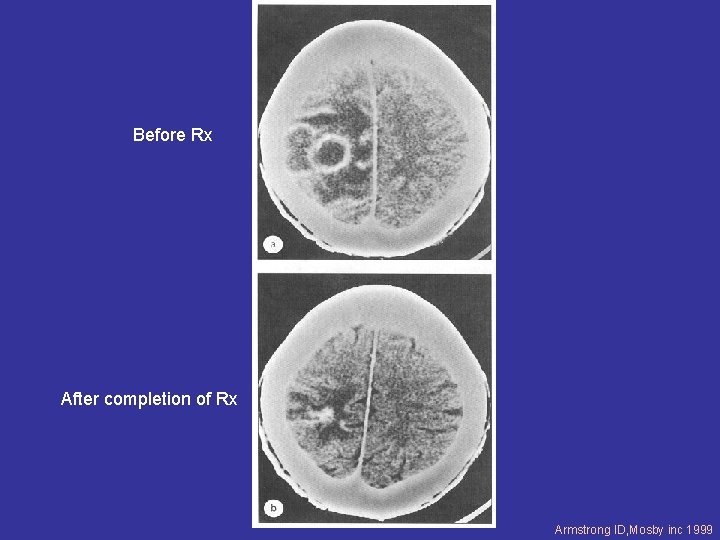

SERIAL IMAGING IMPORTANT TO MONITOR RESPONSE

Before Rx After completion of Rx Armstrong ID, Mosby inc 1999